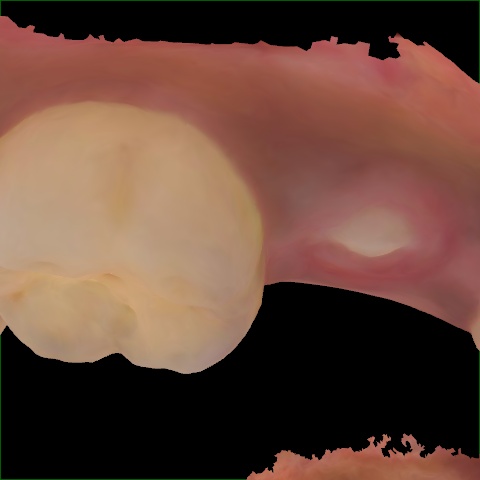

Image 361 / 1715

NHD35761

Annotated as "Good"

Original Image Rendering Image